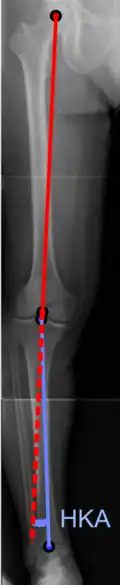

Varus or valgus deformity

There are two disorders relating to an abnormal angle in the coronal plane at the level of the knee:

- Genu valgum is a valgus deformity in which the tibia is turned outward in relation to the femur, resulting in a knock-kneed appearance.

- Genu varum is a varus deformity in which the tibia is turned inward in relation to the femur, resulting in a bowlegged deformity.

The degree of varus or valgus deformity can be quantified by the hip-knee-ankle angle,[36] which is an angle between the femoral mechanical axis and the center of the ankle joint.[37] It is normally between 1.0° and 1.5° of varus in adults.[38] Normal ranges are different in children.[39]

-

Hip-knee-ankle angle by age, with 95% prediction interval.[39]